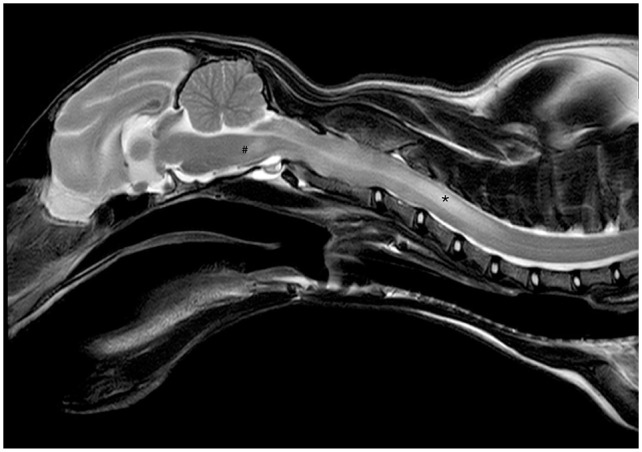

Case summary: A 6-month-old male British Longhair cat presented with acute neurological signs, ocular changes, massive ascites and laboratory parameters consistent with feline infectious peritonitis (FIP). Systemic and neurological signs fully resolved with initial treatment (GS-441524; BOVA UK [15 mg/kg PO q24h for 42 days], levetiracetam [20 mg/kg q8h] and prednisolone [1 mg/kg q24h until day 21]). Lethargy and fever reappeared 17 days after treatment. Four days later, severe multifocal neurological signs re-emerged. High-field MRI revealed multifocal intra-axial and intramedullary lesions in the brainstem and cervical spinal cord, severe meningitis and generalised mild ventriculomegaly. Feline coronavirus (FCoV) RNA was detected in the cerebrospinal fluid by reverse transcription quantitative PCR (RT-qPCR). Abdominal effusion was absent. Serum alpha-1-acid glycoprotein (AGP) was again elevated. FIP re-emergence was suspected, and antiviral treatment was resumed. After 1 day of GS-441524 treatment (15 mg/kg PO q24h), severe hypoventilation developed, requiring intubation and mechanical ventilation for 1.5 days. Treatment was switched to remdesivir (16.7 mg/kg IV q24h, Veklury; Gilead) for 4 days. Oral GS-441524 was then reintroduced (10 mg/kg q12h) and continued until day 84. Treatment resulted in partial recovery with moderate ataxia and reduced left-sided menace response remaining 181 days after starting the second treatment.

病例总结:一只6个月大的雄性英国长毛猫出现急性神经系统症状,眼部改变,大量腹水和实验室参数符合猫感染性腹膜炎(FIP)。初始治疗(GS-441524; BOVA UK [15 mg/kg PO q24h,连用42天]、左乙乙坦[20 mg/kg q8h]和强的松龙[1 mg/kg q24h,连用21天])后,全身和神经系统症状完全缓解。治疗后第17天再次出现嗜睡和发热。四天后,严重的多灶性神经症状再次出现。高场MRI显示脑干和颈脊髓多灶轴内和髓内病变,严重脑膜炎和广泛性轻度脑室肿大。采用逆转录定量PCR (RT-qPCR)方法检测脑脊液中猫冠状病毒(FCoV) RNA。腹部未见积液。血清α -1-酸性糖蛋白(AGP)再次升高。怀疑FIP再次出现,恢复抗病毒治疗。GS-441524治疗1天后(15mg /kg PO q24h)出现严重低通气,需要插管和机械通气1.5天。治疗转为瑞德西韦(16.7 mg/kg IV q24h, Veklury; Gilead),持续4天。然后重新引入口服GS-441524 (10 mg/kg q12h)并持续到第84天。第二次治疗后181天,患者部分恢复,伴有中度共济失调,左侧威胁反应减少。相关性和新信息:这个病例说明了诊断和治疗再出现的fip相关神经症状的复杂性。AGP监测为早期发现复发提供了一种有希望的非侵入性方法。通过适应短期和长期抗病毒治疗并提供重症监护,可以为患有严重复发的fip相关神经症状的猫获得良好的长期预后。